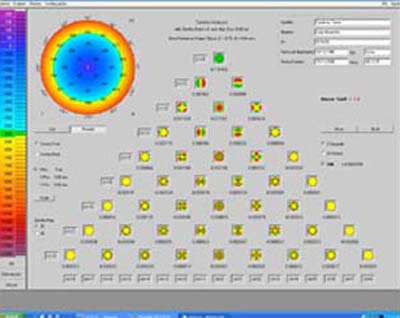

Un frente de Onda es una superficie imaginaria, formada por un haz de luz de rayos paralelos que se propaga a través de un medio. Esta superficie será plana si todos los rayos viajan a la misma velocidad; para la teoría electrodinámica se define como “una superficie de igual fase” En el ojo humano sin defectos, esta superficie imaginaria será curva, porque los rayos paralelos tienen que recorrer diferentes distancias y propagarse a velocidades diferentes a través de la óptica del ojo.

La imagen ideal de un haz de rayos puntual, emitido por un objeto que se encuentra ubicado en el espacio, es un punto sobre la retina (mácula). En un ojo sin defectos, sólo los rayos que pasan por el centro de la pupila lo hacen de una forma regular. Los rayos que entran más periféricos al centro de la pupila experimentan desviaciones direccionales, las cuales pueden ser irregulares y asimétricas. El efecto de las desviaciones direccionales sobre la imagen retiniana es llamada Aberración, porque degrada la imagen y limita la agudeza visual.

Las Aberraciones también pueden ser producidas por pequeñas irregularidades del sistema óptico y tener su origen en la córnea, el cristalino, el vítreo y/o la retina.

Hasta el momento actual únicamente dos aberraciones ópticas podían ser corregidas: El Desenfoque (Miopía, Hipermetropía) y el Astigmatismo; aquellas alteraciones que no se podían corregir con anteojos convencionales, se llamaron Aberraciones de Orden Superior

La Tecnología del Frente de Onda originalmente fue desarrollada hace 50 años para la Astronomía; se utilizó para medir las distorsiones del frente de onda de la luz proveniente de la atmósfera a su entrada al telescopio óptico; al desarrollar controles con óptica adaptativa, se logró mejorar la nitidez de las imágenes estelares. La mayor parte de esta tecnología fue desarrollada alrededor de los años 70, en relación con la investigación de los sistemas de defensa antimisiles.

En Oftalmología el término se ha utilizado para todos los conceptos, instrumentos y aplicaciones desarrolladas para seguir la onda luminosa que penetra al globo ocular y medir las distorsiones que presenta en su curso intraocular.